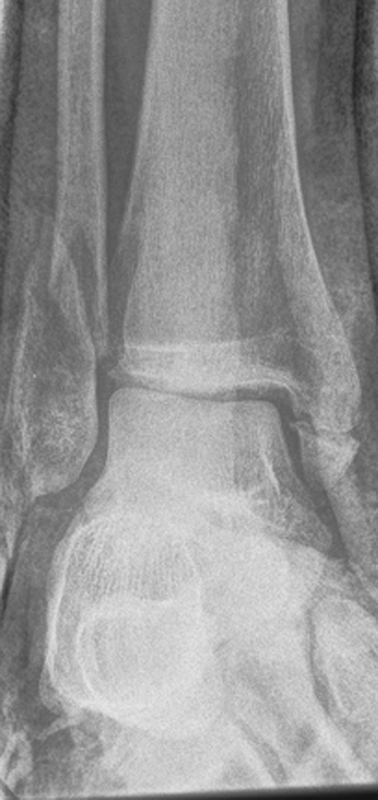

Die Standard-Röntgenaufnahmen des oberen Sprunggelenks bestehen aus drei Aufnahmen: der antero-posterioren Aufnahme (ap), der antero-posterioren Aufnahme mit Innenrotation des Unterschenkels von 20° („Mortise view“), sowie der streng seitlichen Aufnahme (siehe S2-Leitlinie Sprunggelenksfraktur). In der Röntgen-Bildgebung sollte neben den klassischen Frakturzeichen die Integrität der Syndesmose beurteilt werden. Dies erfolgt über die Beurteilung der Breite des lateralen und medialen Gelenkspalts („medial clear space“), des tibiofibularen Abstands 1cm oberhalb des OSG-Gelenkspalts („tibiofibular clear space“), bzw. der tibiofibularen Überlappung. Eine Verbreiterung des tibiofibularen Abstands über 5 mm oder die Erweiterung des medialen Gelenkspalts können Zeichen einer begleitenden Syndesmosenverletzung sein. (Abbildung 3) 6.

Liegt eine Fraktur des oberen Sprunggelenks vor, ist sowohl zur Entscheidung für ein konservatives oder operatives Vorgehen, als auch zur Operationsplanung, ein ausreichendes Verständnis der Fraktur und ihrer Morphologie notwendig. Insbesondere bei komplexen Verletzungen ist dafür die konventionelle Röntgenaufnahme in vielen Fällen nicht ausreichend. So konnten z.B. Black et al. zeigen, dass die operative Strategie zur Versorgung von OSG-Frakturen in 24% basierend auf einer zusätzlichen CT-Bildgebung relevant geändert wurden 7. Dies betraf die Lagerung, die Wahl des Zuganges und die Art der osteosynthetischen Versorgung. Besonders häufig änderte sich das Vorgehen bei Verletzungen des medialen (21%) und des posterioren Malleolus (15%). Darüber hinaus führten dislozierte (dislozierte Frakturen 31% vs. nicht-dislozierte Frakturen 20%) oder komplexe Frakturen (Trimalleolar-Frakturen 29% vs. Unimalleolar-Frakturen 10%) besonders häufig zu relevanten Änderungen des operativen Vorgehens. Die Computertomographie ist daher, insbesondere bei Bi- und Trimalleolar-Frakturen, essentiell für das Verständnis der Fraktur und somit für die Planung und Durchführung der Operation. In Abbildung 4 und 5 sind exemplarisch ein Röntgen- und ein CT Befund gegenübergestellt.